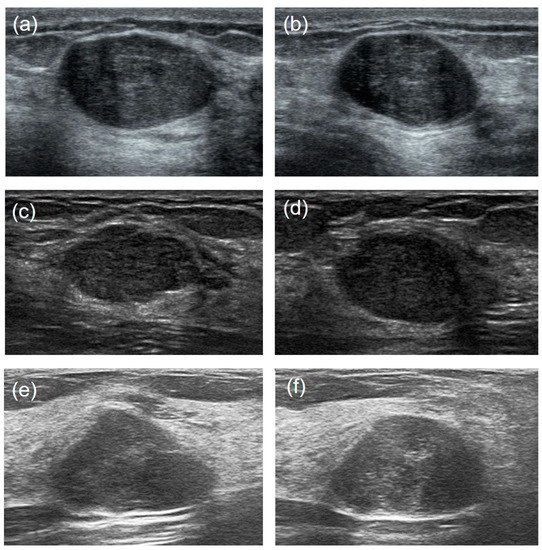

- Image enhancement—the grayscale transformation function was used to enhance the contrast between the foreground and the background of US images. The image enhancement can improve image quality, enrich information, and enhance image interpretation and the recognition effect (Figure 2).